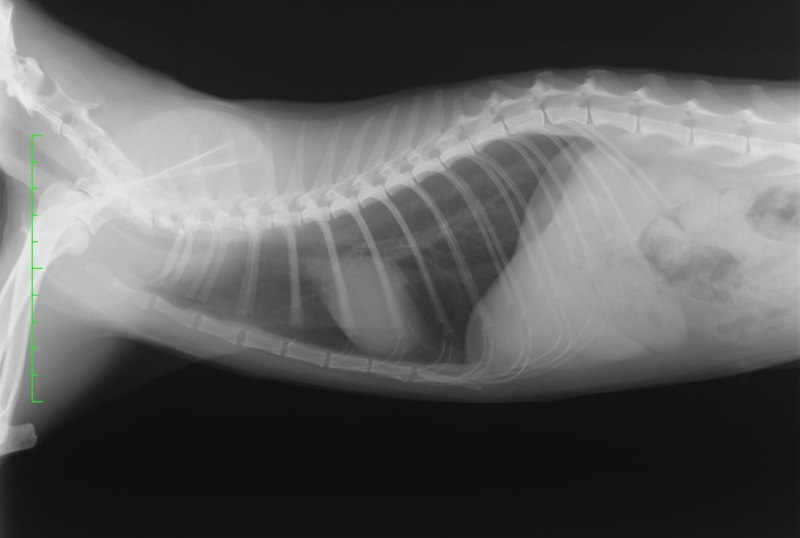

前縦隔型リンパ腫(低分化型) 雑種猫 3歳 ♀猫白血病ウイルス陽性

主訴:食欲低下、えずき、喉元の喘鳴音

身体検査所見:軽度脱水、可視粘膜色正常、心肺音異常なし、腹腔内触知物なし、体表リンパ節腫脹なし

診断:胸部レントゲン検査にて、前縦隔領域に不透過性亢進領域を確認しエコー検査にてFNAを実施。細胞診の結果「低〜中分化型リンパ腫」と診断

治療および経過 :多剤併用療法(UW25プロトコール)を開始。一般状態の改善が認められており、現在も治療中です。

前胸部にみられた不透過性領域の退縮が認められます

猫の前縦隔型リンパ腫は発症に猫白血病ウイルスとの関連があるとされているリンパ腫です。以前は猫のリンパ腫の大部分を占めていましたが、近年は猫白血病ウイルスに罹患している猫が減少している影響により、前縦隔型リンパ腫も減少傾向にあると言われています。前述の通り治療に関する予後や報告は少ないものの、他のリンパ腫と同様に抗がん剤治療への反応がみられるとされています。